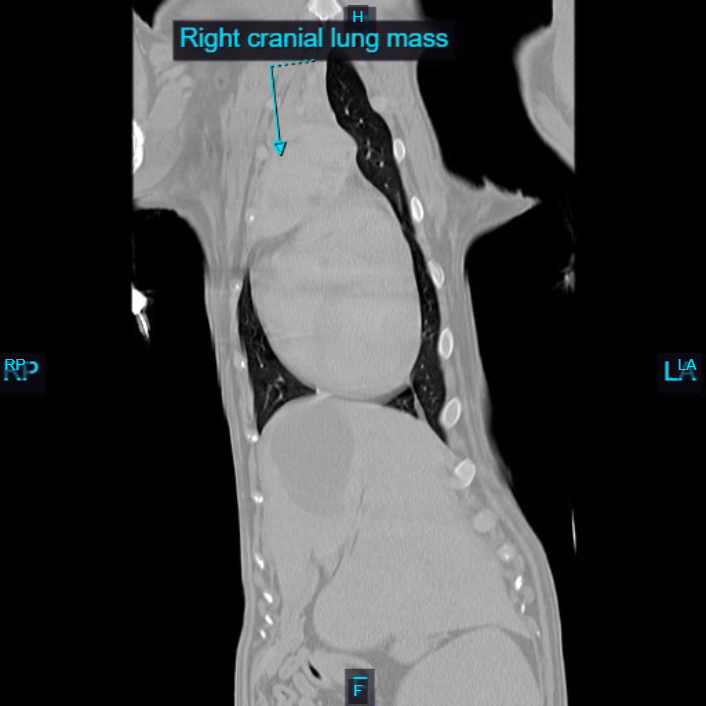

She was seen by Dr. Cletzer on 1-15 for a CT scan and aspirates of the mass. The CT revealed that the mass involved the ventral aspect of her right cranial lung lobe, with local extension into her mediastinum (the tissues in front of the heart and below the lung lobes). Initial cytology raised concern for carcinoma.